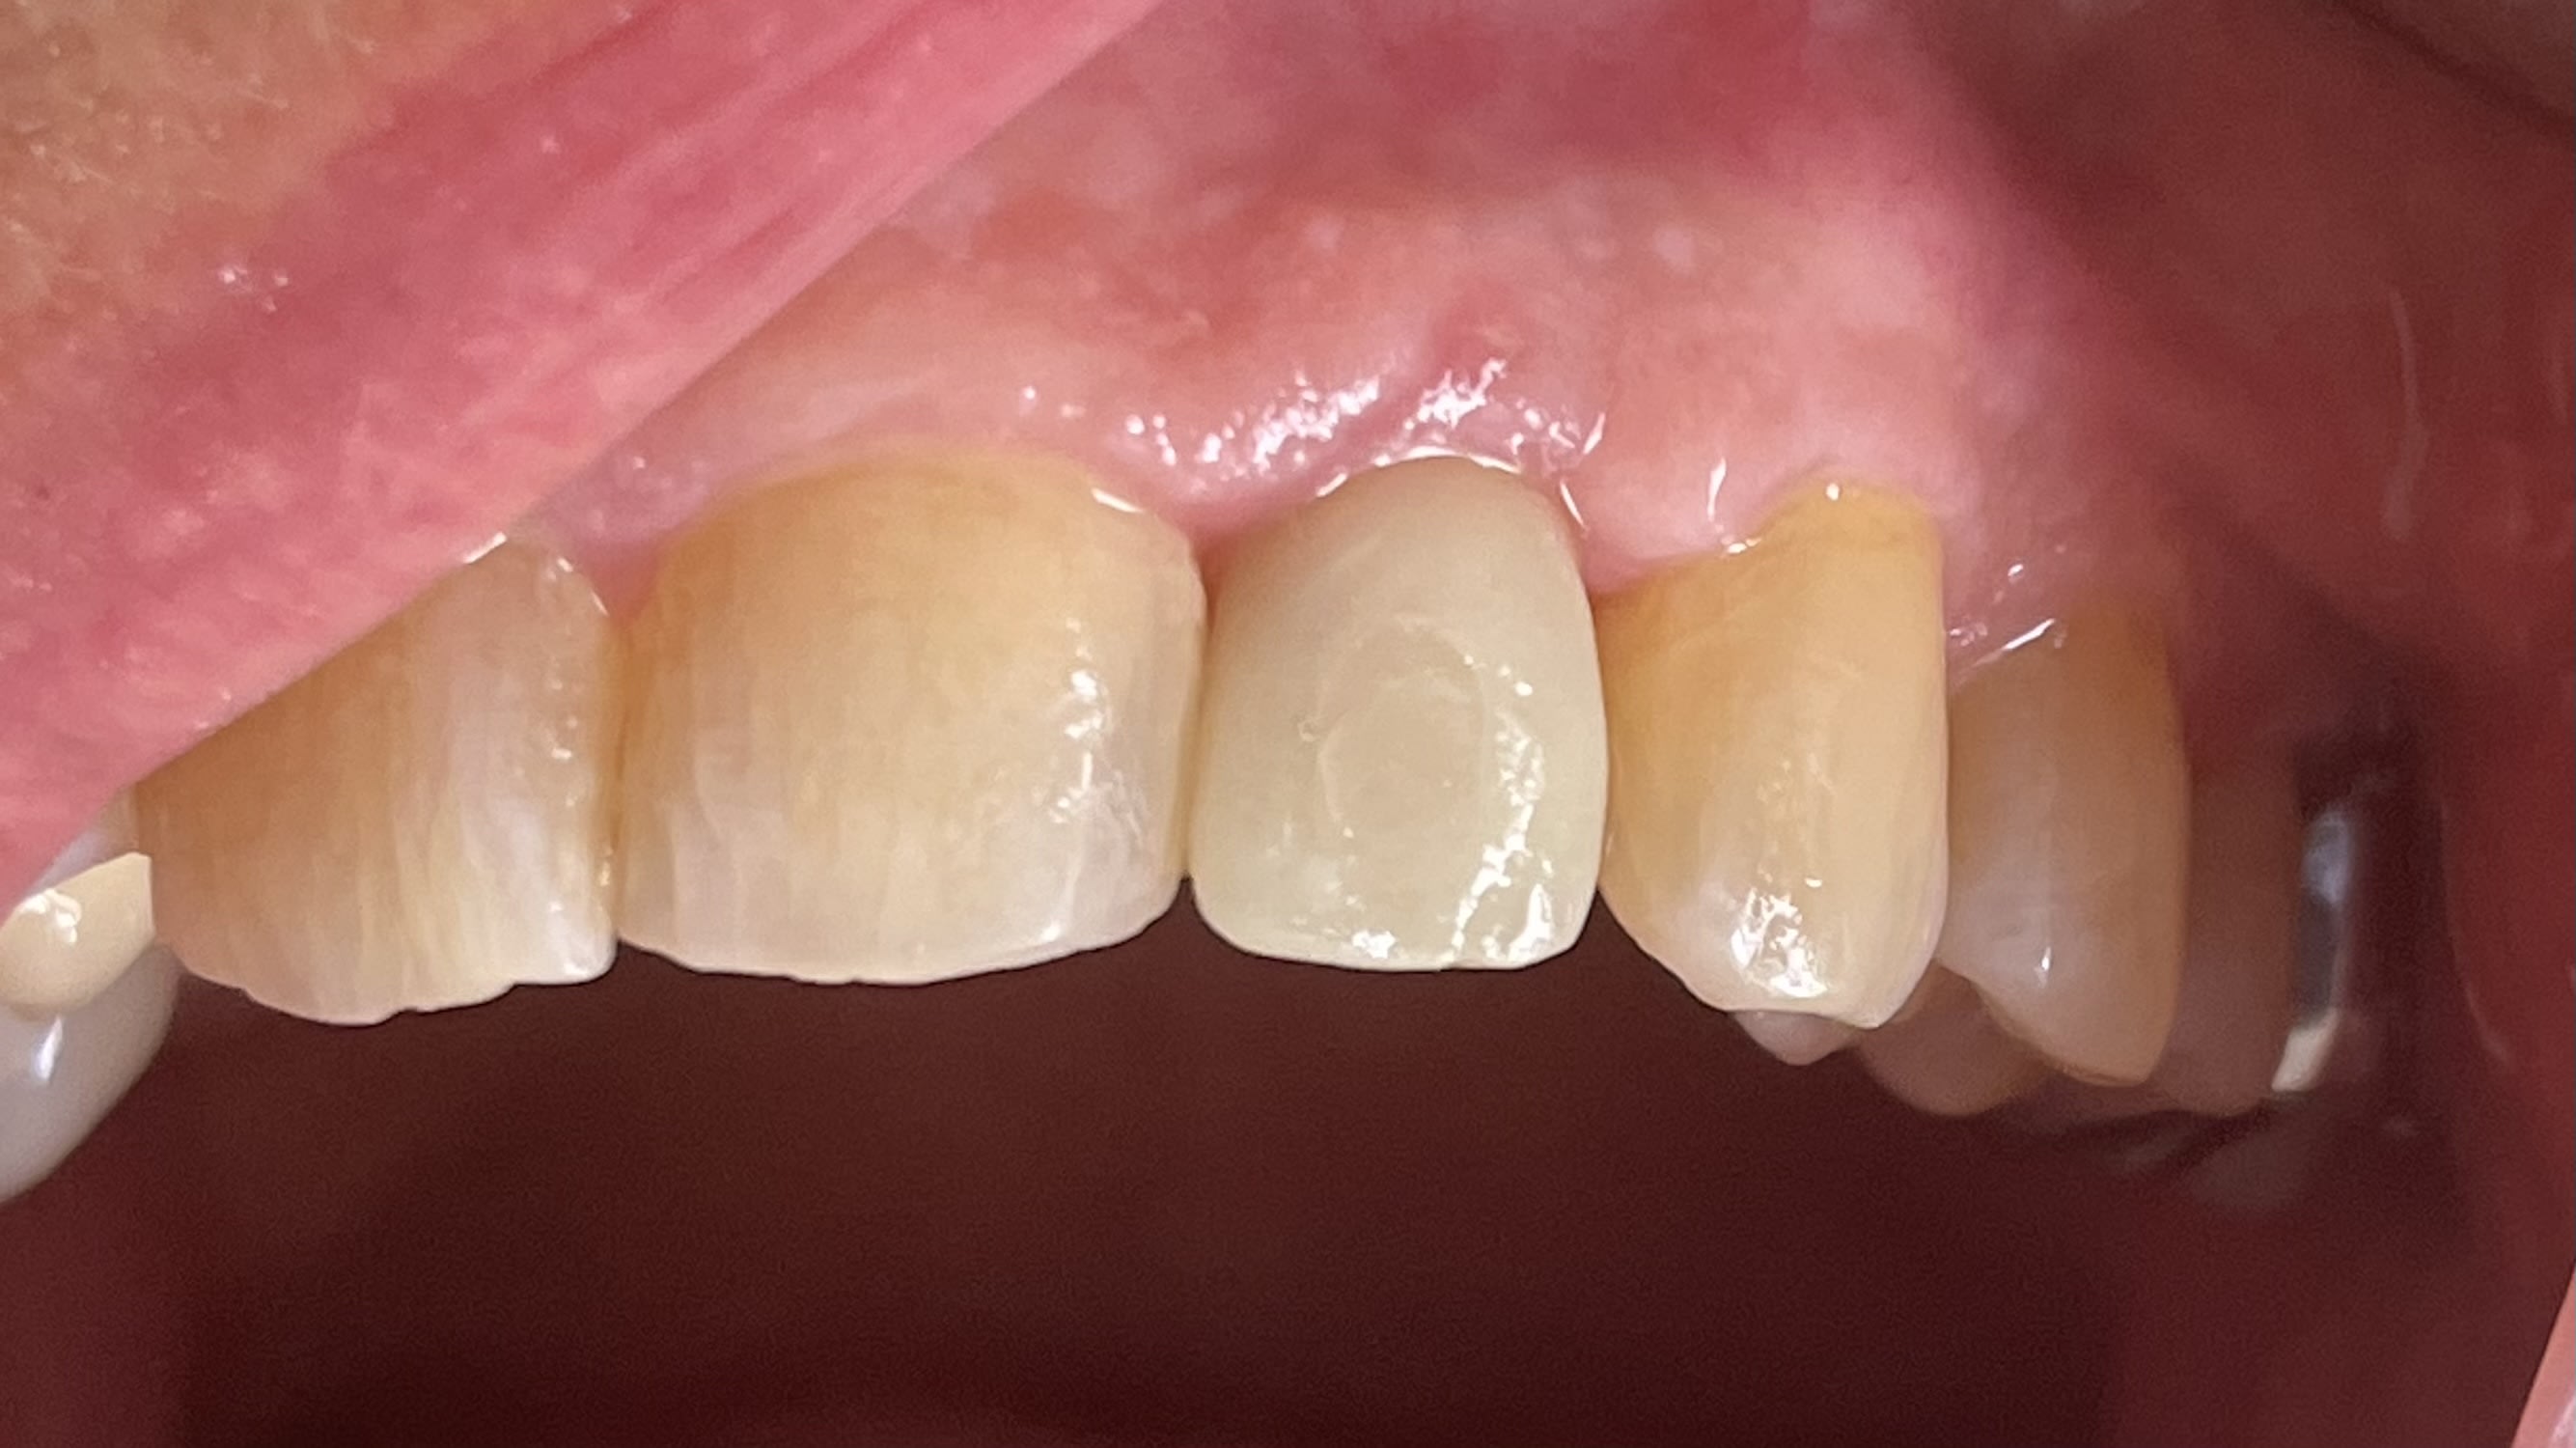

Je n'avais que 6 mm mais pourtant ca passe!